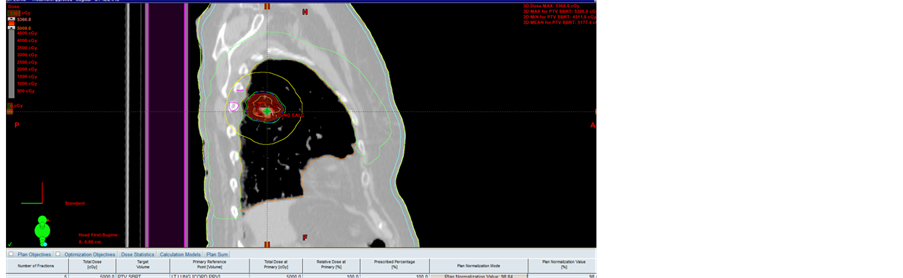

A cohort of thirty-nine patients with stage IA/IB NSCLC underwent definitive thoracic radiation as a single- mode treatment. All of them were treated by SBRT, but they were prescribed a variety of treatment plans. The demographics and stages of the patients are listed in Table 1. Volumetric modulated arc therapy (VMAT) and intensity modulated radiation therapy (IMRT) are the methods of choice for dose delivery; Figure 1 illustrates the VMAT method applied to one patient.

Figure 1. A 72-year-old woman with lung cancer was treated with SBRT for a total dose of 50 Gy in 5 fractions. (a) (top) VMAT with 3 arcs; (b) (middle) isodose lines; (c) (bottom) dose color “wash” normalized to 50 Gy.

more bearable for the patient. The specific advantages of its shorter duration are reduced intrafraction motion by the patient and less loss of biological effect.